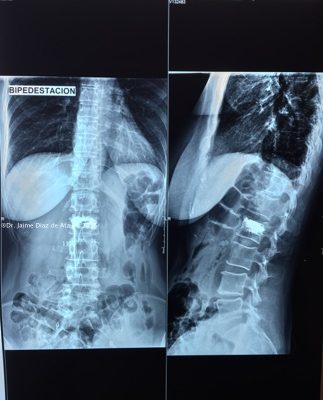

El sistema SpineJack® ha sido diseñado para la reducción anatómica de Fracturas Vertebrales por Compresión (FVC de tipo A1, A2 y A3 según la clasificación de Magerl), con o sin patologías subyacentes que afecten a la calidad del hueso, como la osteoporosis y las lesiones de origen oncológico (metástasis osteolítica o mieloma).

Diversos estudios clínicos y epidemiológicos han demostrado que existe correlación entre la deformación vertebral y problemas clínicos como la cifosis postraumática, que ha sido descrita como una de las deformidades postraumáticas potencialmente más graves. En este contexto, Vexim ha diseñado el implante SpineJack® para ofrecer al médico una solución totalmente controlada y completa para el tratamiento de las FVC, que permite primero una reducción anatómica y después una estabilización segura.

La operación es un procedimiento quirúrgico mínimamente invasivo (incisión pequeña) destinado a restaurar la forma inicial de la vértebra fracturada. Puede realizarse en una sala de radiología o en un quirófano, siguiendo unas normas muy estrictas de seguridad y asepsia.